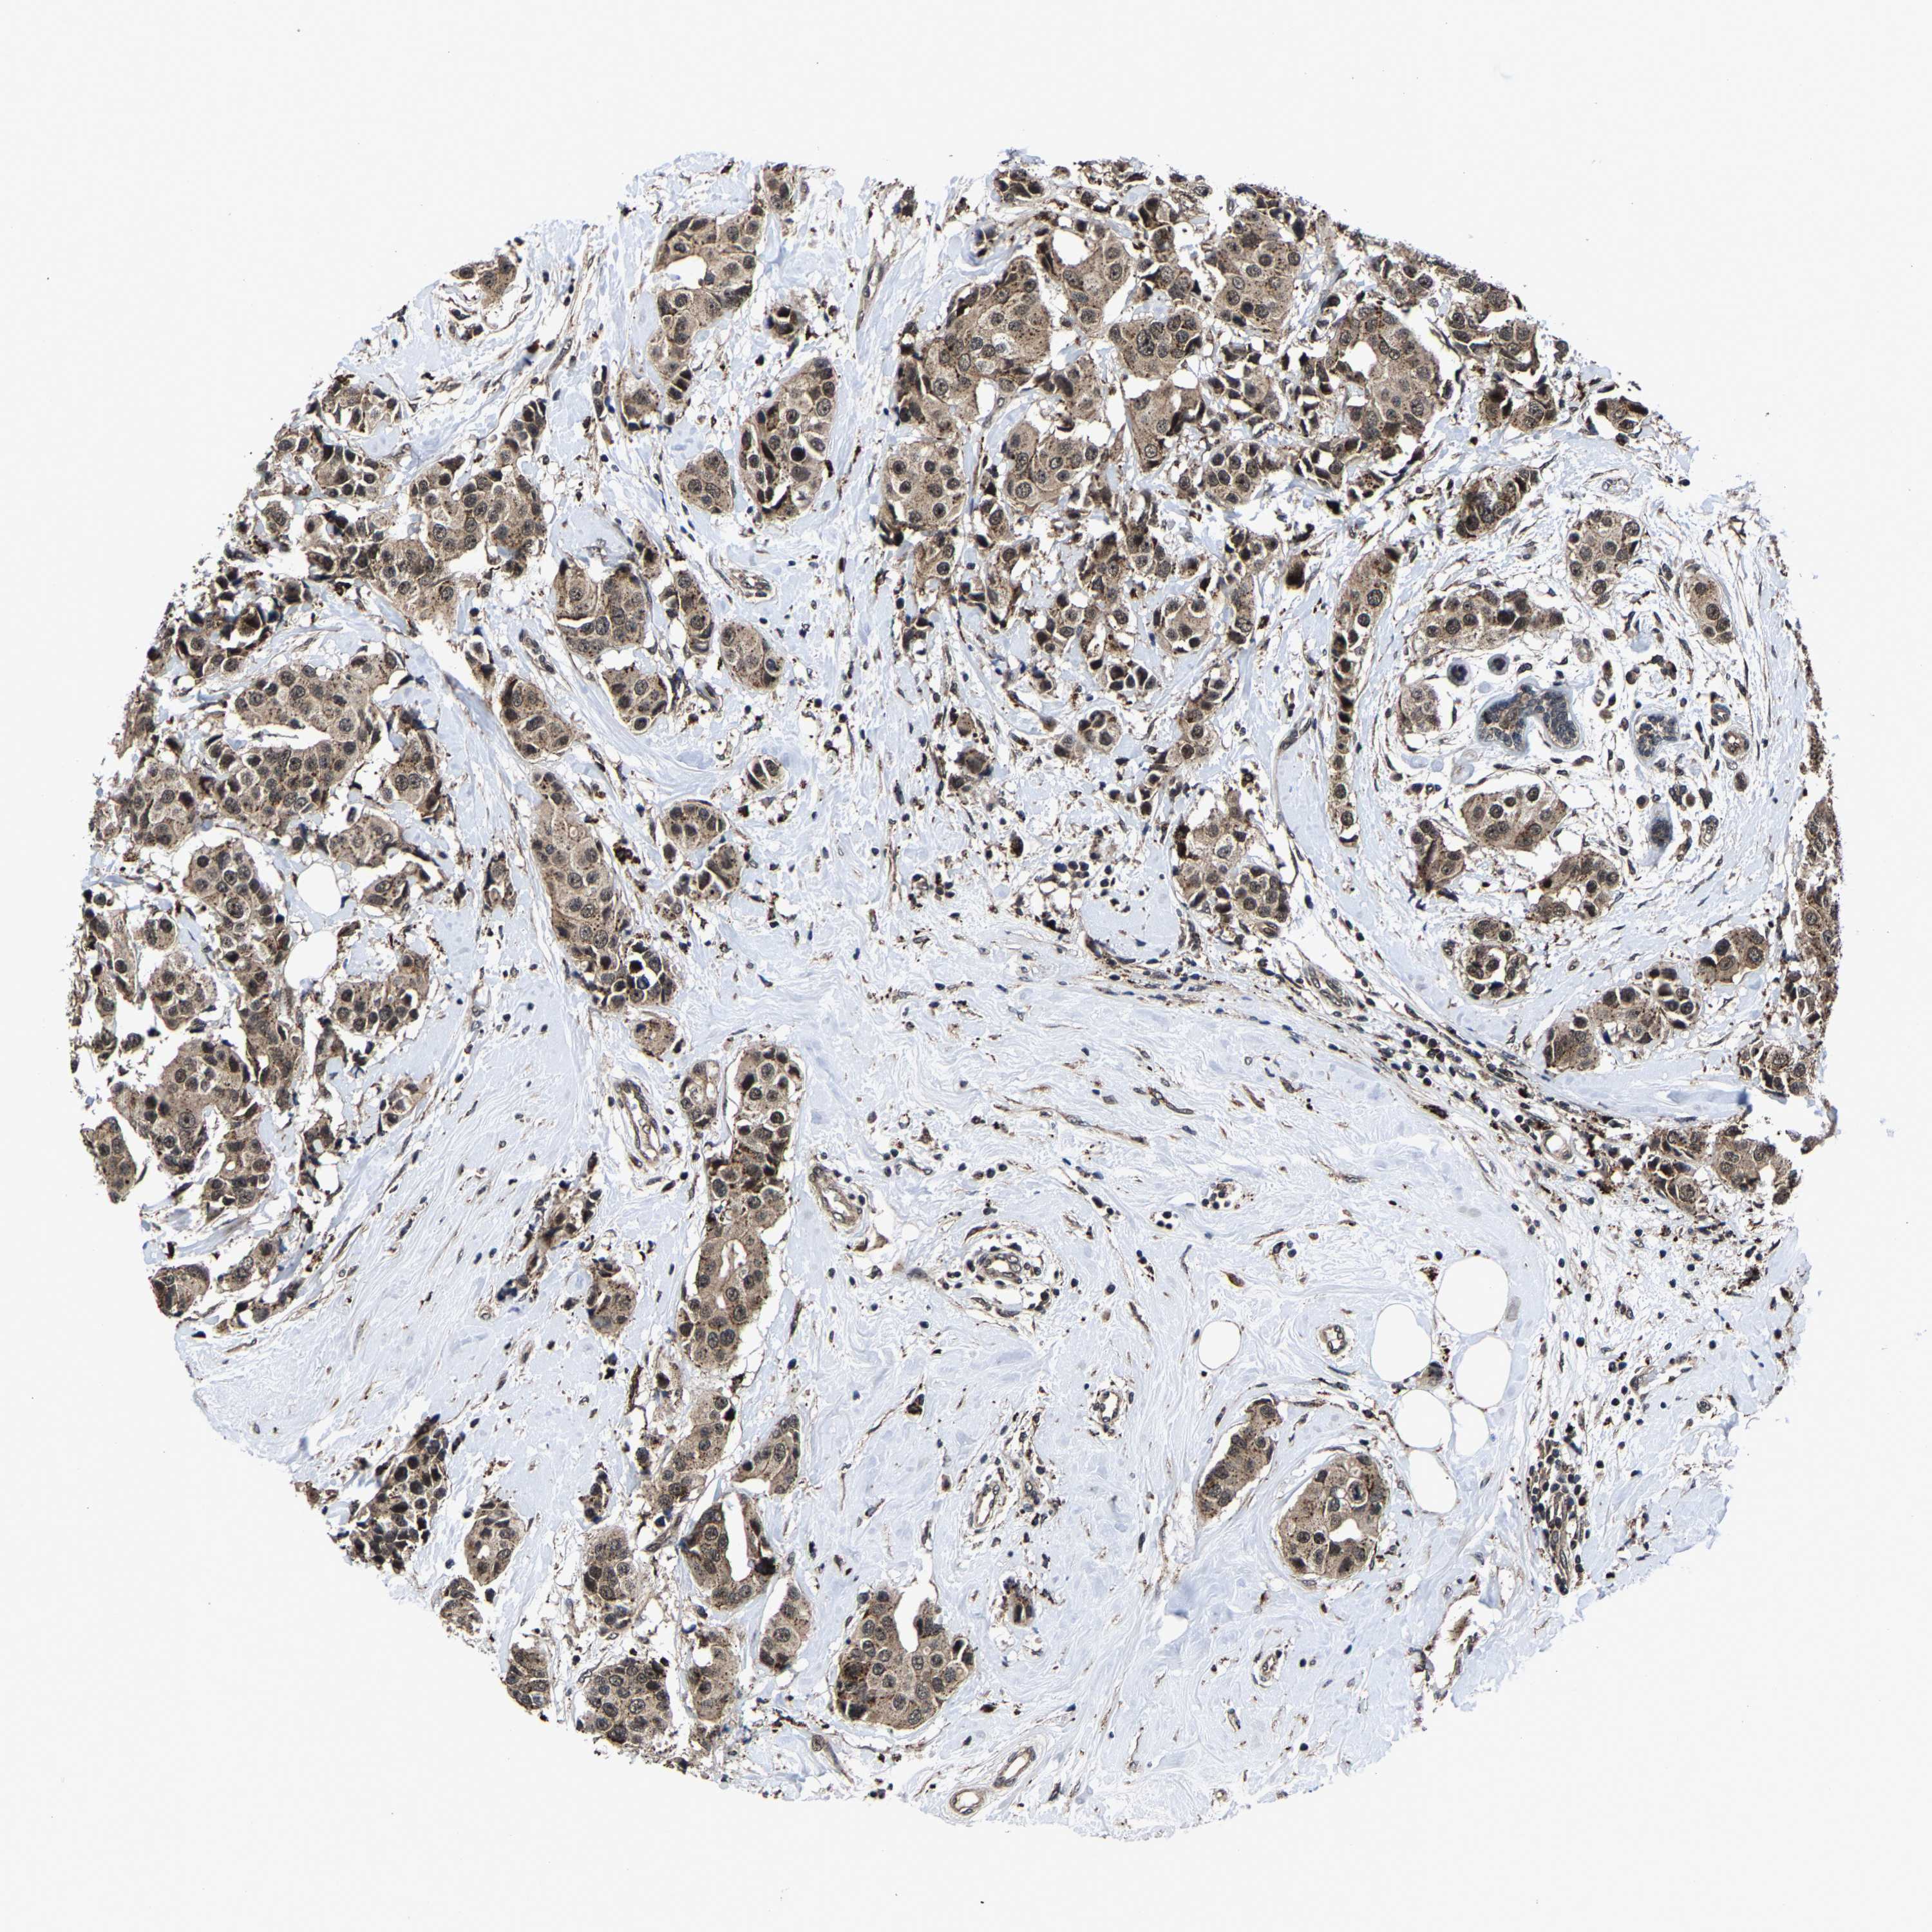

CANCER BREAST CANCER Show tissue menu

BRCA TCGA BRCA VALIDATION PROTEIN EXPRESSION

Breast cancer

Human cancer

Breast invasive carcinoma